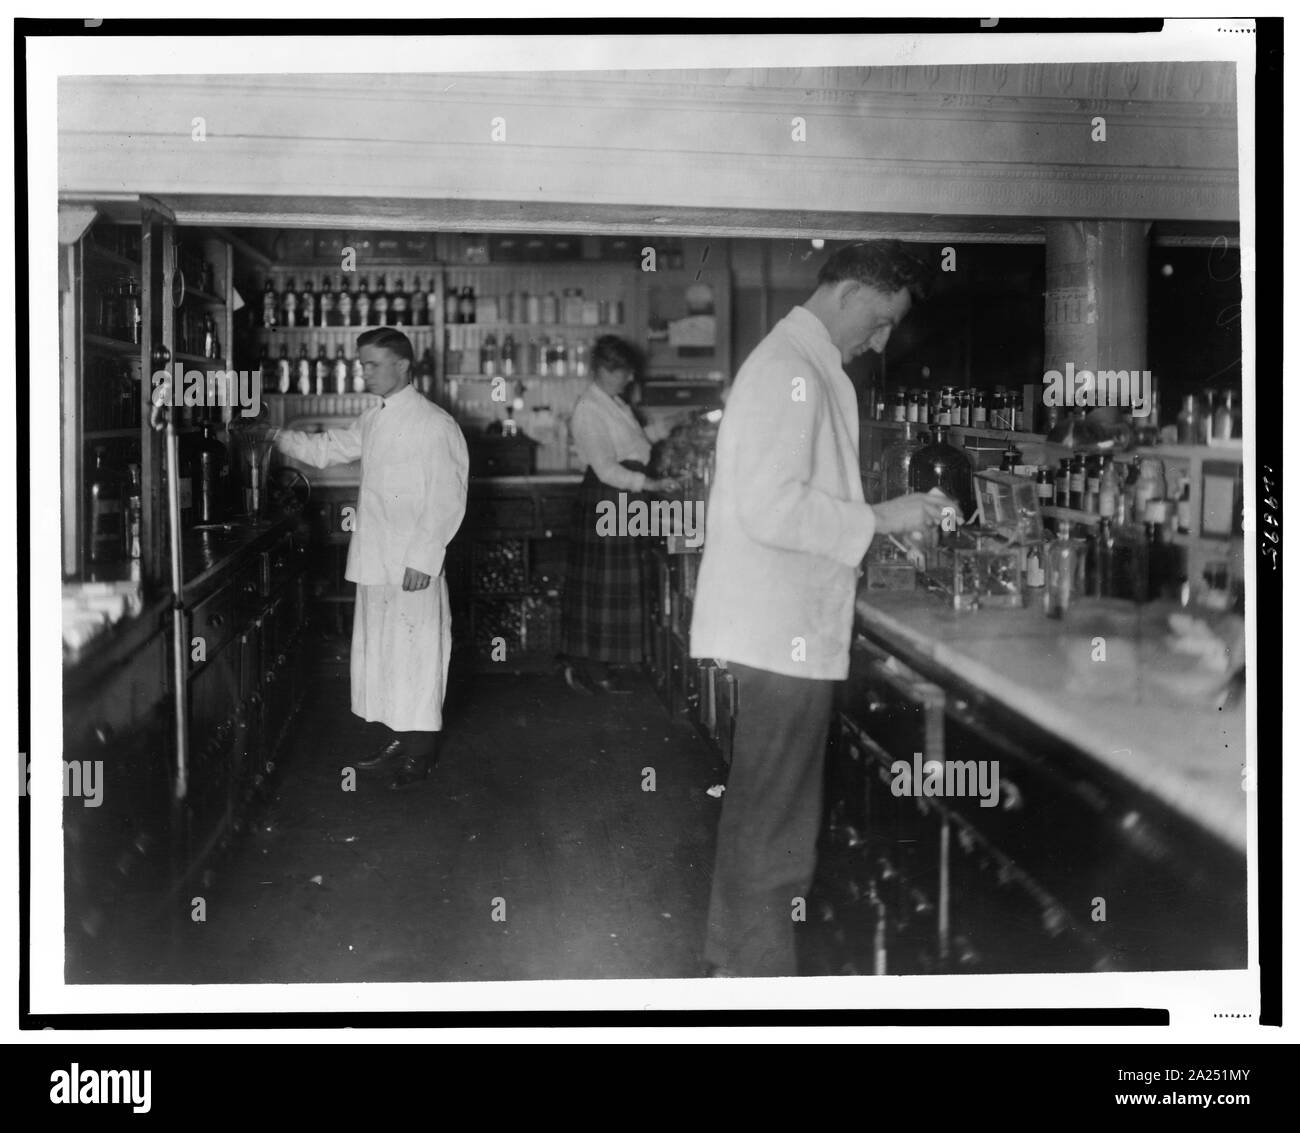

RM2A251KM–Il farmacista a persone di Drug Store, n. 5, 8 e H strade, N.E., Washington D.C., guardando a prescrizioni() sul contatore in camera rivestita con ripiani di bottiglie di farmacia

RM2A251MY–Farmacisti a persone di Drug Store, 7 e E STRADE, N.E., Washington D.C., a contrastare la preparazione di farmaci